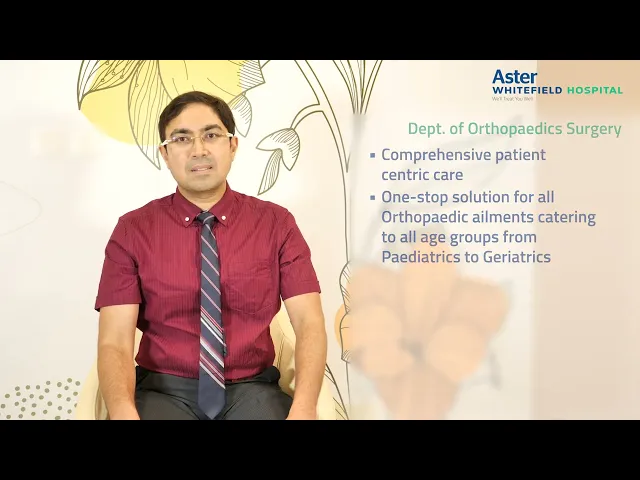

Robotic Joint Replacement & Advanced Sports Orthopedic Care

At Robotic Joints & Sports Ortho Centre, patient care is guided by precision, innovation, and experience. Dr. Kumardev Arvind Rajamanya specializes in robotic-assisted knee and hip joint replacement and sports orthopedic treatments, helping patients regain pain-free movement, mobility, and long-term function. Every treatment plan is designed with a strong focus on accurate diagnosis, advanced surgical techniques, and structured recovery support.

Robotic Joint Replacement Expertise

Dr. Kumardev Arvind Rajamanya specializes in robotic-assisted knee and hip replacement procedures, offering improved surgical precision, better implant alignment, reduced pain, and faster post-operative recovery.

Personalized Recovery & Performance Care

Each patient receives individualized attention, clear guidance, and structured rehabilitation support designed for long-term joint health, improved strength, and optimal movement.

Advanced Orthopedic Services Focused on Robotics & Sports Care

At Robotic Joints & Sports Ortho Centre, Dr. Dr Kumardev Arvind Rajamanya offers specialized orthopedic services with a strong focus on robotic-assisted joint replacement and sports injury management. Every service is guided by precision, advanced techniques, and a patient-first approach aimed at restoring mobility, strength, and performance.

At Robotic Joints & Sports Ortho Centre, Dr. Dr Kumardev Arvind Rajamanya offers specialized orthopedic services with a strong focus on robotic-assisted joint replacement and sports injury management. Every service is guided by precision, advanced techniques, and a patient-first approach aimed at restoring mobility, strength, and performance.